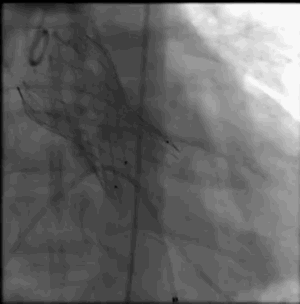

术中影像

主动脉根部造影

导丝跨瓣

选择BaIt23球囊进行预扩

结合术前CT判断和术中影像判断,最终决定植入L26号venus A瓣膜。采取标准位置释放。

瓣膜释放完成左右冠显影良好 瓣膜最终形态

L26号瓣膜释放,BaIt23预后扩,几乎无瓣周漏,压差解除